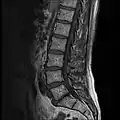

MRI lumbar spine with degeneration (sagittal T1 FSE)